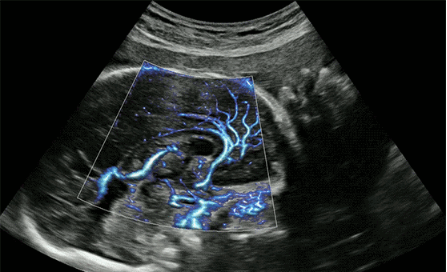

CrystalLive?是三星最新的超聲成像引擎,同時增強了2D圖像處理能力、3D渲染能力和彩色信號處理能力,能夠在復(fù)雜情況下提供出色的圖像性能,具備檢測外周血管、微循環(huán)血流的能力。